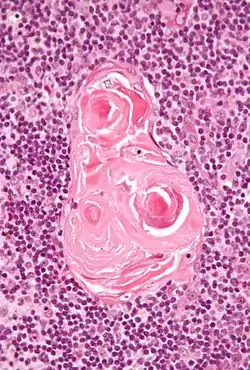

![]() Micrograph of a thymic corpuscle. H&E stain. | |

Hassall's corpuscles (or thymic corpuscles (bodies)) are structures found in the medulla of the human thymus, formed from eosinophilic type VI epithelial reticular cells arranged concentrically. These concentric corpuscles are composed of a central mass, consisting of one or more granular cells, and of a capsule formed of epithelioid cells. They vary in size with diameters from 20 to more than 100μm, and tend to grow larger with age.[1] They can be spherical or ovoid and their epithelial cells contain keratohyalin and bundles of cytoplasmic fibres.[2] Later studies indicate that Hassall's corpuscles differentiate from medullary thymic epithelial cells after they lose autoimmune regulator (AIRE) expression.[3] They are named for Arthur Hill Hassall, who discovered them in 1846.[4][5]